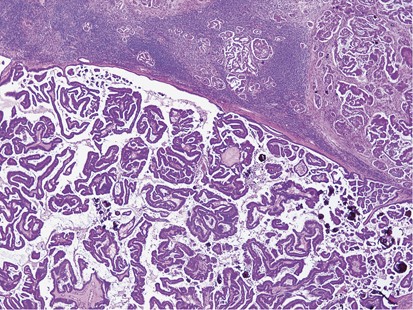

Glass slides were available for review in 53 out of 85 (62%) cases. These slides included 28 core biopsies and 30 excisions (5 cases with both cores and excisions). Seven cases involved lymph nodes only (6 axillary and 1 intramammary). The remaining 46 cases all involved the breast. Mammary lymphatic only involvement, without stromal invasion, occurred in 7% (3/46) of the cases. Certain recurrent histological features were identified, including a well-circumscribed nodule (74%, 34/46), often surrounded by a fibrous pseudocapsule (52%, 24/46) with varying thickness (Figure 1) and absence of an in situ mammary carcinoma. Interestingly, in the great majority of the tumors, lymphovascular invasion was notably absent (87%, 40/46). Tumoral calcifications were observed in non-mammary metastases of serous carcinoma type that were psammomatous in nature (75%, 6/8) (Figure 2), including two cases that involved lymph nodes.

Several recurrent histological features were identified in metastatic tumors to the breast. These included a well-circumscribed lesion, sharply demarcated from the adjacent tissue and the absence of in situ carcinoma and calcifications.2, 5, 30, 32 The exception to this is serous ovarian carcinoma, which very frequently has psammomatous calcifications.8, 9 These features contrast with primary breast carcinoma, as it is usually an ill-defined lesion, infiltrates breast parenchyma, and often contains in situ carcinoma and calcifications (non-psammomatous). While most studies have found similar results, in the series by Lee et al,4 calcifications were identified in one hepatocellular carcinoma and two gastric carcinomas metastatic to the breast.